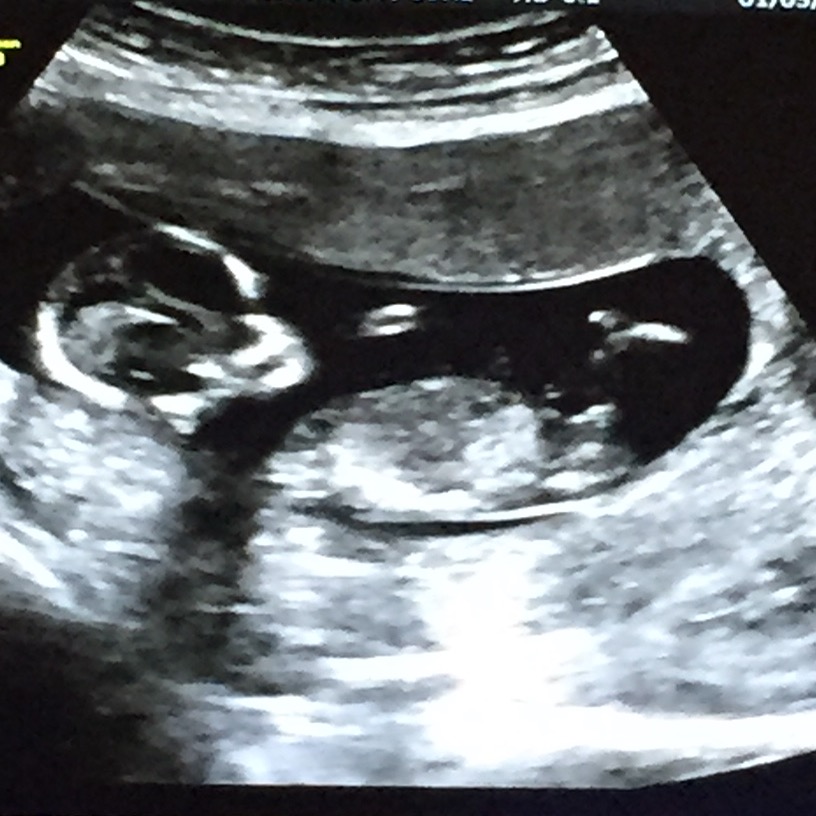

Technician and perinatologist won't tell me anything, please help! =)

Looks like a boy!!

The dangle has an angle, boy guess!

Major stacking at both gestations, I really think that's a boy!

Any girl guesses? Can I start buying blue? :DS: I didn't know it's that obvious… I really hope it doesn't change in a few weeks...